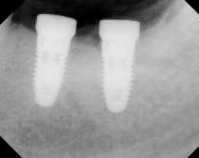

![]() Final Restoration 1 Year After Implant Replacement |

![]() Final Restoration x-ray 1 Year After Implant Replacement |